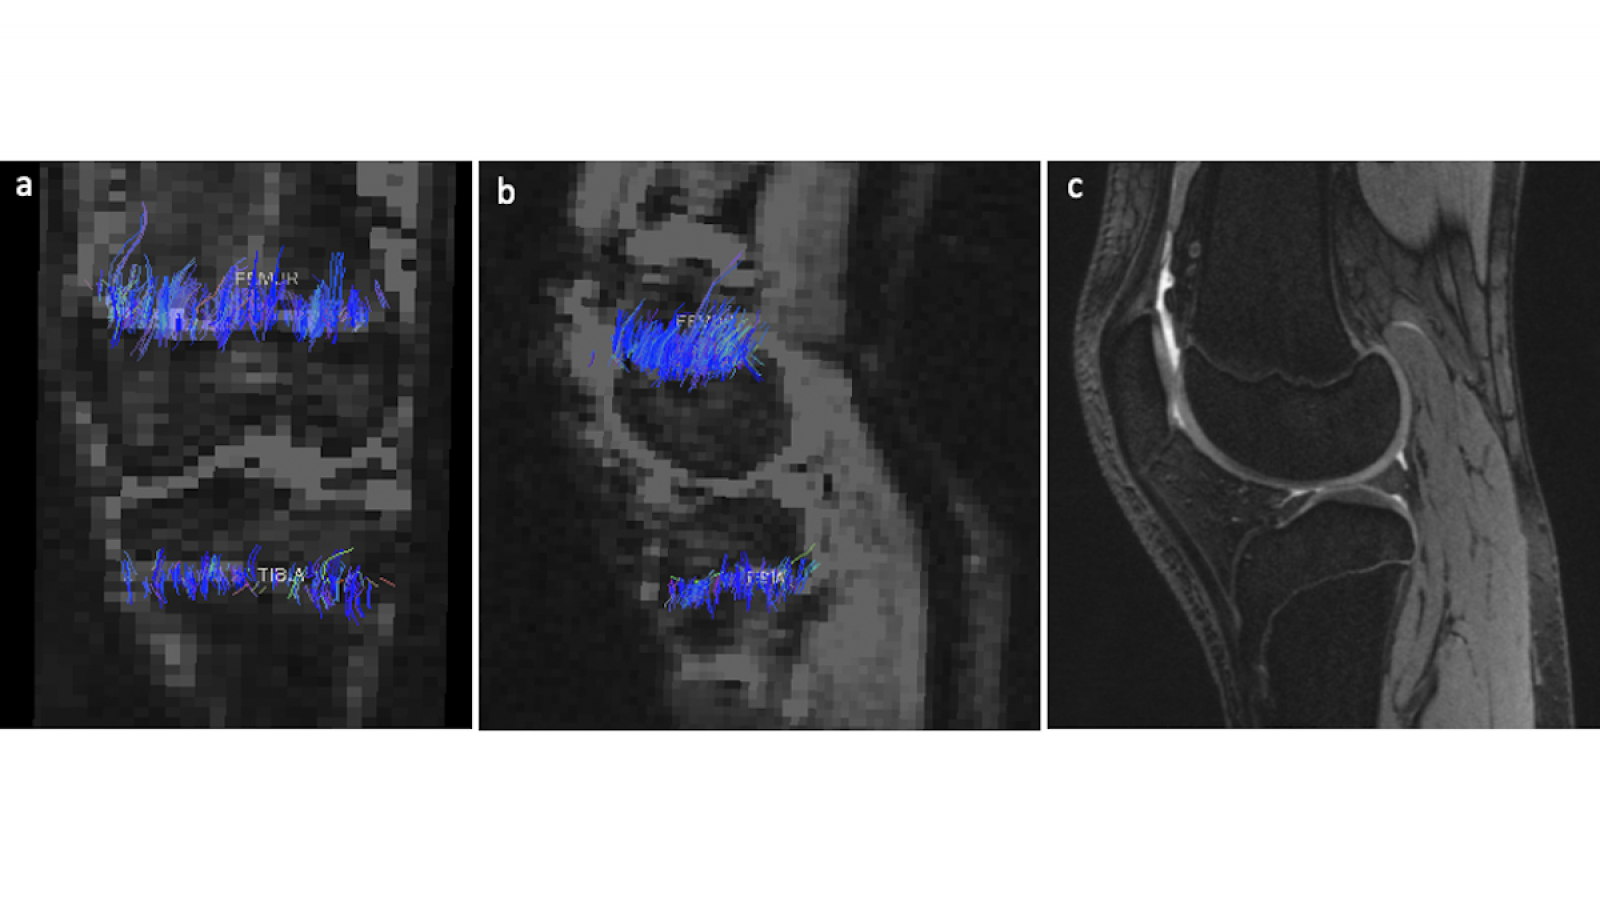

- Summary: We measure height velocity during early puberty and serial changes in physeal DTI tract volume in children imaged at 0, 4, 8, and 12 months and then annually during the four years of the growth spurt.

- Summary: We correlate physeal DTI parameters with decreasing height gain in adolescents studied for two years near skeletal maturity.

- Summary: We measure tract volume and FA in children before growth hormone (GH) therapy and 4, 8, and 12 months later to assess GH response sooner than current methods.

Validation of Diffusion Tensor Imaging of the Physis and Metaphysis as Predictor of Skeletal Growth in Children

- Summary: Tract volume derived from DTI of the physis/metaphysis can predict height velocity (1-yr. height gain) and total height gain more accurately and precisely than current bone age-based methods.